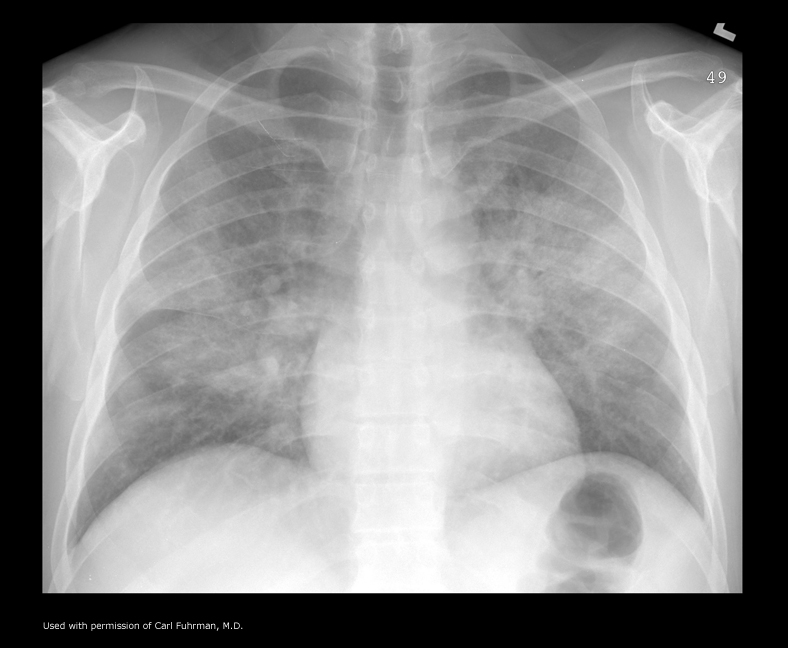

What is going on in this radiograph?

PCP pneumonia

This sort of very diffuse reticular pattern is highly suggestive in the right clinical context, and you might consider ordering an HIV test.